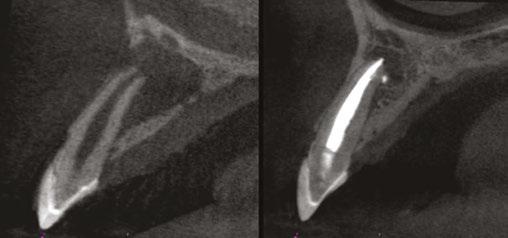

Judy McIntyre, DMD, MS Figure 1: Acutely curved and calcified buccal canal right under upper left premolar crown margin; valuable information for access and management. No. 9 also has a PARL, which was only incidentally captured Figure 2: Large PARL with destruction of the maxillary sinus floor and sinusitis as a result

About 10 years after completing residency, I opened my own practice and invested in a DEXIS CBCT. Initially, I only used it for apicoectomies and retreatments. In time, I began to realize how helpful it was for all my cases. With the 3D-scan information (Figure 1), I could have saved myself some humbling experiences and surprises. Endodontists hate surprises, and we really hate failures! Once I started using my CBCT more frequently, I was able to appreciate things that would have otherwise been intra-op surprises and plan for them prior to starting the procedure. The 3D data allows me to properly assess prognosis, determine the best course of treatment, and plan that treatment with a level of precision that is impossible otherwise.

Figure 7: Planned-for access with the scan info on this extremely calcified canine Figures 8 and 9: 8. Deep distal split with PARL. 9. Missed buccal canal; history of previous RCT, post, crown and apico Figure 10: Retreatment consultation. PA from GD Figure 11: Scan images show a previously existing strip perforation

what the literature suggests. And, when I know how many and where the canals are (Figure 13), I can take measurements on the scan and work more efficiently — measuring my working lengths of each canal, appreciating severe curves or calcifications, and knowing where canals can be expected to be located, again, rather than removing unnecessary tooth structure to find if it is there, or not!

As an endodontist, I often treat heavily restored teeth. I am often planning my accesses based on the scan’s information. This saves time and conserves more tooth structure. I’m not looking for canals that may or may not be there, and I’m looking for canals under the targeted/planned access — with the scan, I have an actual map (Figure 7)! CBCT directs me where to go and where to end. It reveals anomalies, which are more common than we think, so I can avoid iatrogenic incidents and provide less invasive treatments. Lower second molars with only two canals occur — often!

I’m also changing my treatment plans based on the data from my CBCT. Sometimes I look at a root canal treated PA and presume I know what I will do: a retreatment or an apico. Another recent, poignant case: a lower incisor with a previous RCT and a previous apico (Figure 9). Usually, once a tooth has had an apico, there may not be much left to offer and most of the time, the default is another apico, especially as there was very little room for an implant on the lower anteriors. I scanned the tooth and saw that a whole canal had been missed — twice! The RCT and the apico had left the buccal canal completely untouched. I changed my treatment plan based on this information!